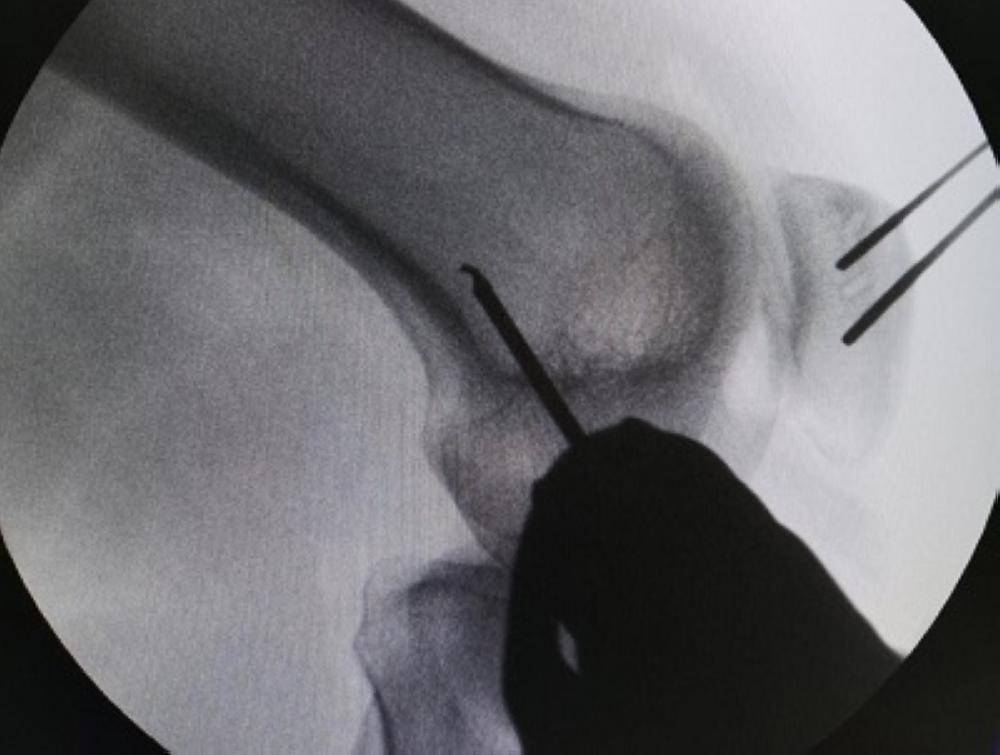

تَمَكّن فريق طبي متخصص في الإصابات الرياضية بمستشفى عسير المركزي، من إجراء أول عملية من نوعها بمستشفيات منطقة عسير، وهي عملية ترميم وزراعة للرباط الصابوني الجانبي الداخلي بواسطة منظار الركبة المتطور، لشاب كان يعاني من آلام في مقدمة الركبة وعدم ثبات بالصابونة.

وفي التفاصيل، حضر شاب يبلغ من العمر ١٩ عاماً لعيادة وحدة الإصابات الرياضية والمناظير بمستشفى عسير المركزي، وكان يعاني من آلام في الركبة، وبأخذ تفاصيل التاريخ المرضي والفحص السريري والأشعات اللازمة؛ تَبَيّن أنه يعاني من قطع في الرباط الجانبي الداخلي للصابونة بالركبة اليمنى.

وبيّنت صحة عسير، أنه تم وضع الخطة العلاجية اللازمة له من قِبَل استشاري جراحة العظام والإصابات الرياضية والمناظير في المستشفى الدكتور فايع عسيري، ومن ثم إجراء العملية بمستشفى أحد رفيدة العام ضمن البرنامج المشترك بين مستشفى عسير المركزي ومستشفى أحد رفيدة العام، لإنهاء قوائم الانتظار بالإصابات الرياضية، وخروج المريض وهو بصحة وسلامة، وتم البدء في برنامج العلاج الطبيعي وإعادة التأهيل المتبعة في مثل هذه الحالات.